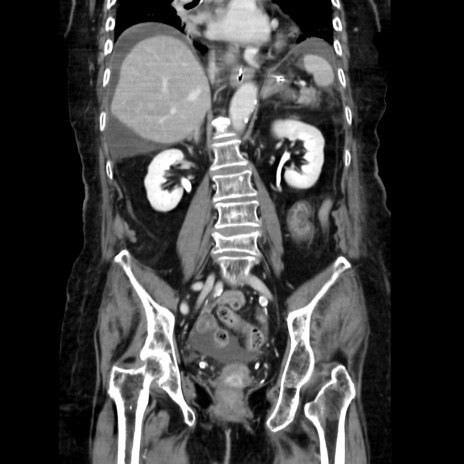

症例40(冠状断像)

【症例】90歳代女性

【主訴】腹痛・嘔吐

【現病歴】 食欲低下、嘔吐があり昨日他院受診。肺炎と診断され入院となる。入院後より腹部全体に圧痛あり。胃管留置され経過みていたが、症状持続するため、

当院転院となる。

【既往歴】胸椎圧迫骨折、胆石症

【身体所見】腹部:中央に激痛あり、圧痛あり、反跳痛不明

【データ】WBC 17100、CRP 18.82

冠状断像